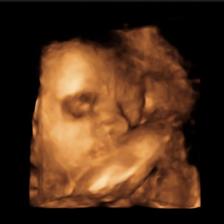

Naše první radost ❤️

Dne 8.2.2020 to celé začalo ❤️

Dne 11.3.2020 se to celé potvrdilo ❤️

Dne 24.10.2020 v 2:30 se to malé narodilo ❤️

Náš syn Martínek 👶❤️

Vážil: 3070g

Měřil: 49cm